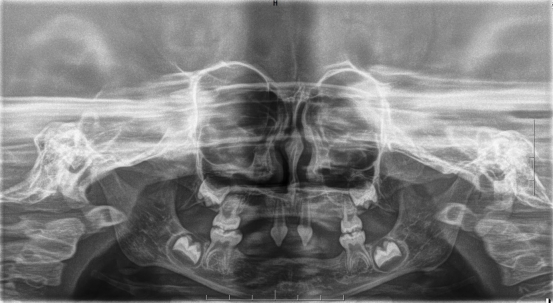

患者4岁,乳牙未正常萌出,上颌仅4下颌仅2颗乳牙,不能正常咀嚼,于2022年底在外地就诊多次无法修复,专程到口腔医院就诊。在后疫情时期,患者经王永门诊诊治后商讨出诊疗方案医院细心安排,于222由王永带领谭雯珈、姜炜鹏等医师,使用修复、正畸、修复工艺等多项技术,顺利完成了大面积乳牙缺失修复患儿现场进食效果良好,家长及患儿十分满意。

因其口腔表征为先天缺牙甚至无牙颌,且缺牙患儿口内余留牙往往表现为锥形牙、釉质发育不良、牙槽嵴发育不良等,可严重影响患儿的咀嚼功能及面部软硬组织生长发育。

目前观点普遍认为,患儿在早期进行修复治疗可以促进其颌骨及颞下颌关节发育,也可尽早恢复发音、咀嚼、吞咽功能,因此口腔修复治疗应在患儿颌骨和牙齿发育成熟之前进行。

根据临床经验,普遍认为传统义齿(通常为可摘局部义齿或全口义齿)修复时机为患儿可配合口腔修复治疗的过程,并且有自主佩戴义齿的能力时。对处于生长发育期的外胚层发育不全患者,因其颌骨发育、牙齿萌出和种植体之间的相互影响尚未完全明确,种植时机的选择仍存在争议。